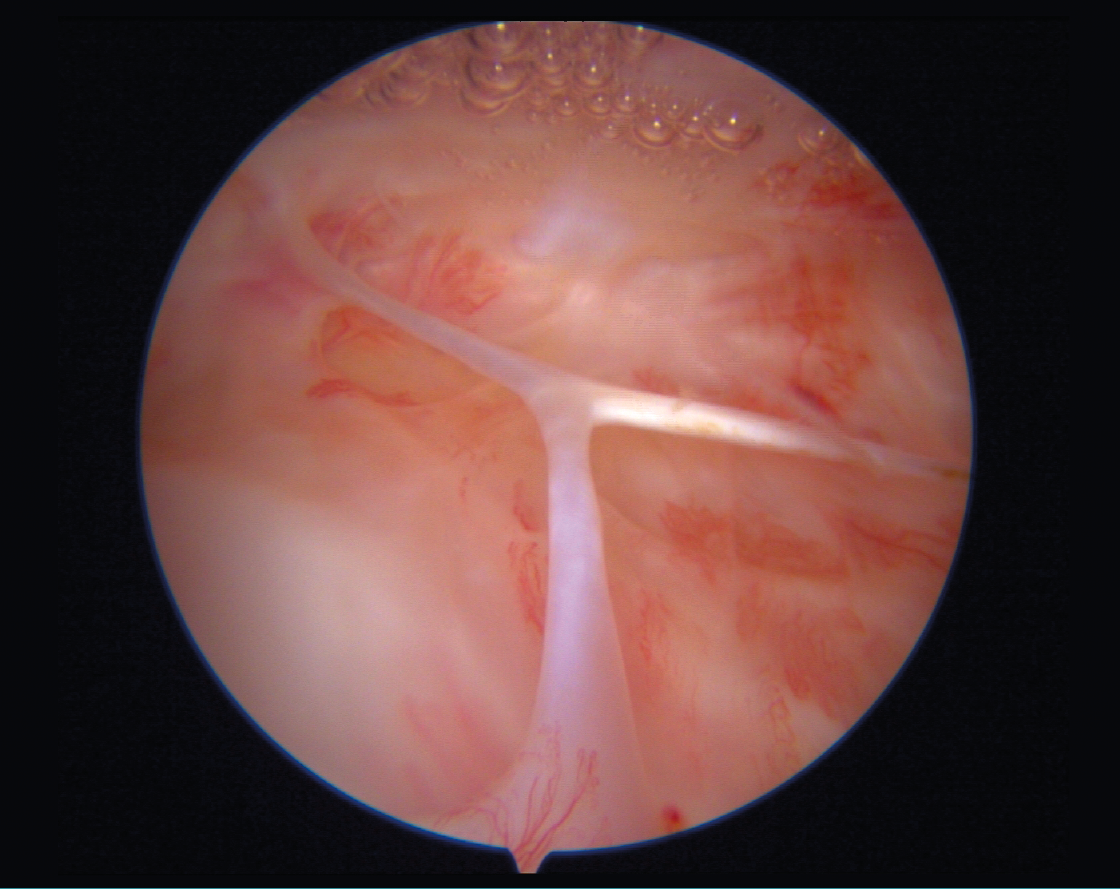

- Paz en nuestro mundo